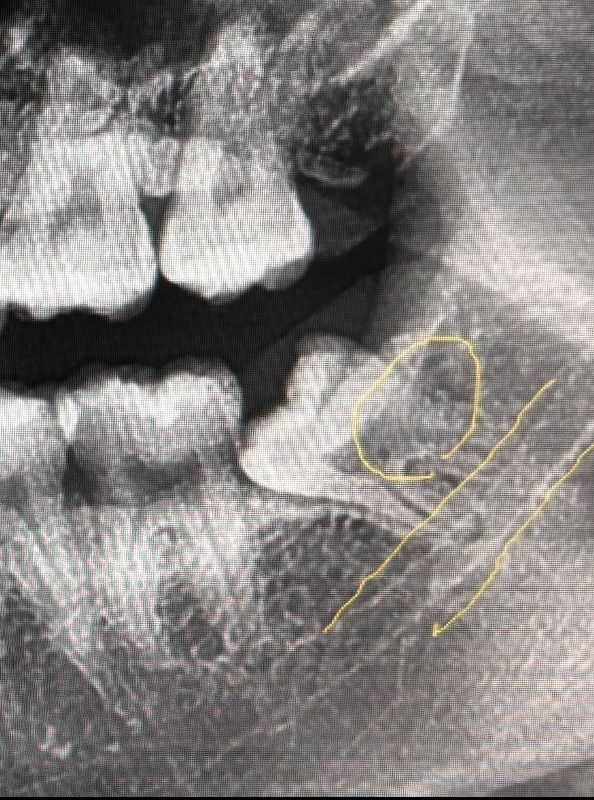

이런 사랑니 동네 치과 말고 전문병원에 가야하나요? + 아래 두개 한 번에 뽑는 건 비추인가요?

1. 사진 첨부한 사랑니 잇몸 안 뚫은 상태고 신경쪽이라고 합니다. 이거 전문 병원에 가는 게 나을까요?

2. 아래쪽에 사랑니가 두개 있는데 하나는 위에서 말한 상태고 반대쪽 건 신경과 안 닿아있고 잇몸 밖으로 3/4 정도 드러나 있습니다. 다른 어금니들처럼 곧게 자라있어요. 이 두개 한 번에 뽑아버리면 많이 힘들까요?? 밥을 며칠동안 제대로 못 먹을까요ㅠ 4일까진 버틸만할 것 같은데

현재 매복사랑니가 기울어 있는 경우 신경을 건드릴수 있어 까다로운 발치이기에 구강외과 전문의가이 있는 치과 병원이나 대학 병원에 방문하여 치료를 받는 것이 안전합나더,

사랑 내 뿌리가 신경관과 가깝게 위치된 것으로 보입니다. 있기 때문에 큰 병원에서 발치를 하는 것이 권유되긴 합니다. .

정확한건 CT를 찍어봐야 알겟지만 신경과 치아가 겹쳐 잇다면 사랑니 전문 병원에서 발치를 하시는게 좋을것같습니다.